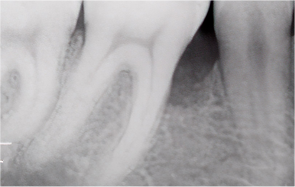

치주질환이란?

‘잇몸병’이라고 불리는 치주염은

잇몸과 잇몸뼈(치조골)를 파괴하는 대표적인 질환입니다.

초기에 단순히 잇몸이 붓고

피가 나는 수준에서 시작하지만,

방치하면 치조골이 점차 흡수되어

결국 치아를 발치해야 하는 상황까지 이어질 수 있습니다.

초기 치은염

잇몸이 붉어지고 붓거나 양치할 때 출혈 발생

중기~만성 치주염

치아가 흔들리고 잇몸이 내려가 뿌리가 드러남